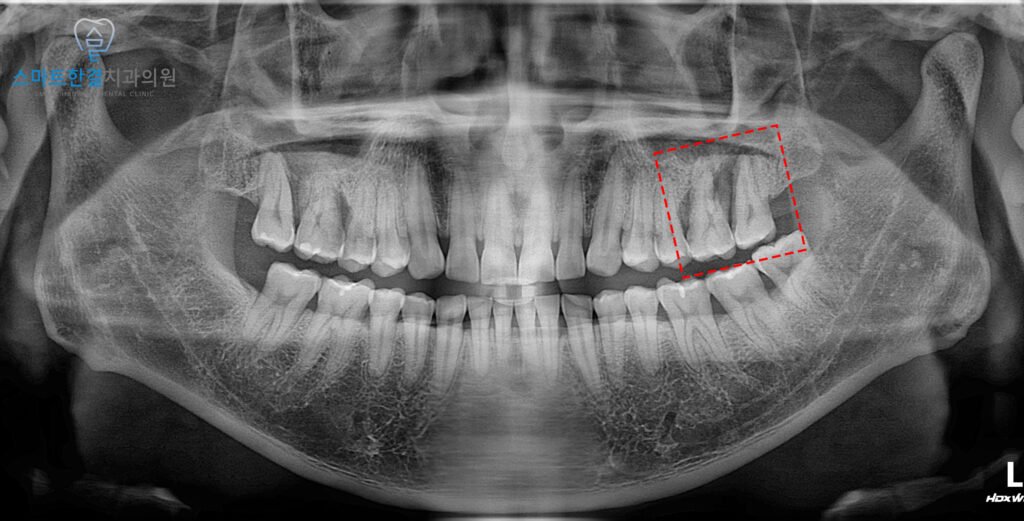

위 환자분께서는

왼쪽 위 치아의 흔들림과

불편함으로 인해

본원에 내원해 주셨어요.

왼쪽 위 큰 어금니 두 개에서

치주염이 발생한 것이

확인되었어요.

치주염으로 인해 골 소실이

빠르게 진행되어,

치아가 흔들리고 그로 인해

통증이 생긴 것으로 보였어요.